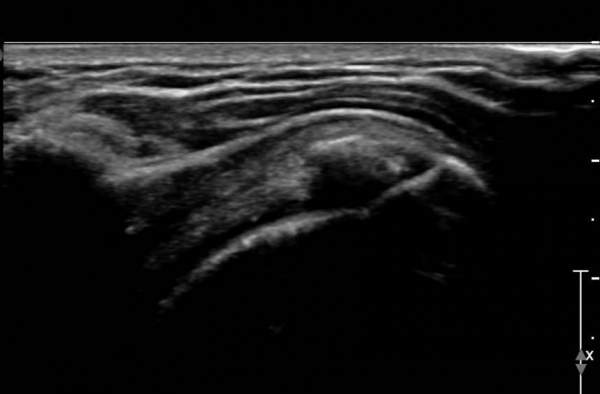

ÃÊÀ½ÆÄ °Ë»ç :  ¿À±¸µ¹±â °ßºÀÀδë Á¾´Ü¸é°Ë»ç¿¡¼­ ÀÎ´ë ½ÉÃþ¿¡ ¼ö¾×Àú·ù°¡ °üÂûµÇ´Âµ¥(»çÁø 1) ÀÌ °ÍÀº

¸¸¼ºÀûÀÎ Ãæµ¹ÁõÈıºÀ» ¾Ï½ÃÇÑ´Ù.

°ß°©ÇÏ±Ù°Ç Á¾´Ü¸é°Ë»ç(»çÁø 2)¿Í ȸ´Ü¸é°Ë»ç(»çÁø 2)¿¡¼­ ÈĹæÀ½¿µÀ» º¸ÀÌ´Â °í¿¡ÄÚ ¼®È¸°¡

°üÂûµÈ´Ù. Åë»óÀûÀÎ °ß°©ÇÏ±Ù°Ç Á¾´Ü¸é°Ë»ç¿¡¼­´Â °ß°©ÇÏ±Ù°Ç »óºÎ ¼®È¸È­·Î º¸ÀÌÁö¸¸ Ⱦ´Ü¸é°Ë»ç·Î

º¼ ¶§ °ß°©ÇÏ±Ù°Ç ÇϺο¡ ¹ß»ýÇÑ ¼®È¸ÀÓÀ» ¾Ë ¼ö ÀÖ´Ù.

¿ªµ¿Àû°Ë»ç¿¡¼­ ¼®È¸°¡ °ßºÀ°ú Ãæµ¹ÇÏ´Â °ÍÀ» È®ÀÎÇÒ ¼ö ÀÖ´Ù(÷ºÎ µ¿¿µ»ó 1).